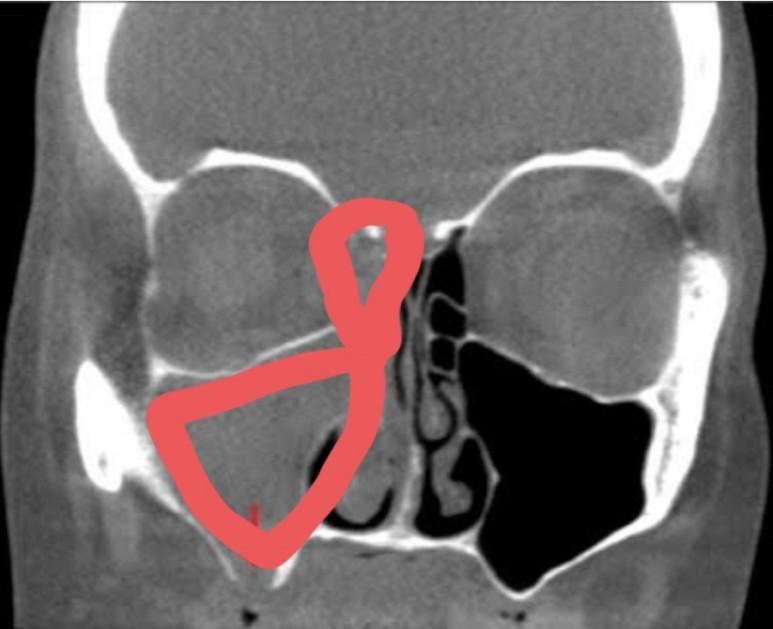

비강과 부비강을 잇는 좁은 문과 같은 입구가 붓고 콧물이 제대로 순환되지 않으면 코와 눈 주위에 그림처럼 빈 공간이 있는데, 비어 있어야 하는 분홍색과 하늘색 부분에 고름이 올라오는 것을 부비강염이라고 합니다.

그래서인지 그 부위를 만질 때 통증도 같이 있었는데 저같은 경우에는 오른쪽 그림의 빨간색으로 체크했듯이 미간과 눈 앞 꼬리에서 눈 밑까지 누르면 상당히 아픈 통증이 있었습니다.광대뼈 아래 뺨의 부부가 누르지 않아도 뻣뻣해지는 느낌이 들었고 #관자놀이의 통증과 치통이 심했어요.

제 엑스레이는 아니지만 가능한 한 비슷한 사진을 보면 위의 사진처럼 붉은 부분이 반대쪽처럼 검게 비어 있어야 하는데 사진처럼 곪아 있더군요.

콧물이 순환하는 입구의 점막이 부어 있고, 양쪽이 딱 붙어 있었습니다. ;;;